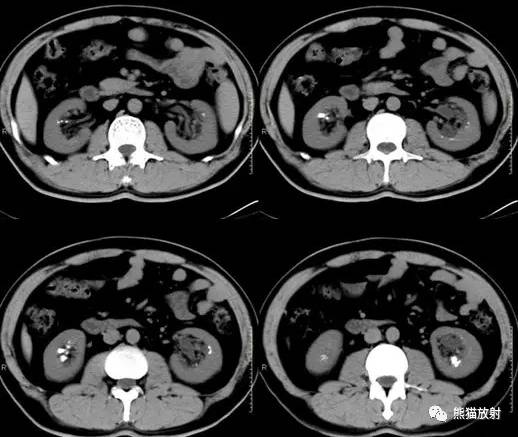

Scout, coronal precontrast, axial nephrographic/excretory phase images, and volume-rendered coronal reconstructions of the left and right kidneys are shown below.

定位像、冠状平扫、轴位排泄期图像及左、右肾冠状VR重建如下所示。

CT urogram (2017): Noncontrast images demonstrate multiple bilateral nonobstructing renal calculi, the largest measuring 6 mm in the right kidney. Some of the calcifications could represent nephrocalcinosis — for example, those in the upper pole of the right kidney. The kidneys show symmetric enhancement without suspicious renal mass. Multiple bilateral exophytic simple renal cysts are noted, the largest in the midpole of the right kidney measuring 3.6 x 4.3 cm. There are additional subcentimeter low-attenuation lesions that are too small to characterize. There is a “paintbrush sign” appearance to the renal medullae in keeping with a history of medullary sponge kidney. There is mild bladder wall thickening and trabeculation that may be related to chronic outlet obstruction. Further evaluation is deferred to cystoscopy.

CTU:CT平扫可见双肾多发非梗阻性肾结石,右肾最大者直径约6mm,其中一些钙化可能代表肾结石,例如,右肾上极的那些。肾脏对称性强化,未见可疑肾肿物。双肾可见多发单纯性肾囊肿,大者位于右肾中部,大小约3.6 x 4.3 cm;另可见不足1cm的低密度灶,其太小而不能显示。肾髓质表现为“毛刷征”,符合髓质海绵肾。膀胱壁轻度增厚并小梁形成,与慢性流出道梗阻有关。进一步评估需膀胱镜检查。

男,41岁,临床发现双肾结石10年。